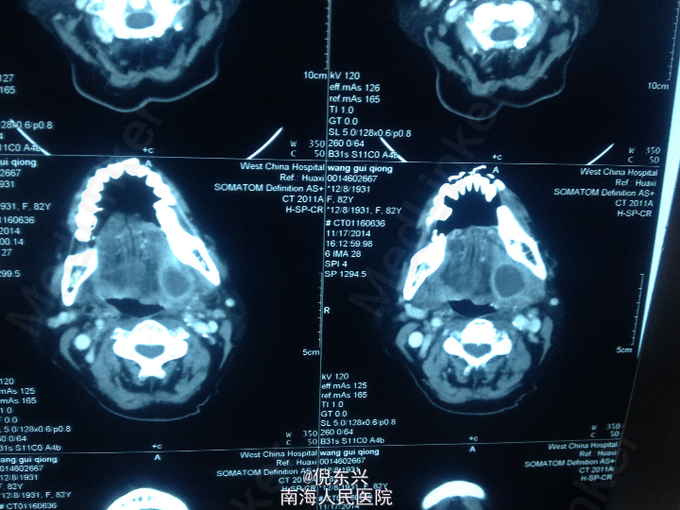

检查见:左侧颌下腺分泌功能下降,左侧颌下区有压痛,口内可触及一硬物 CT检查可见左侧可见一0.5*0.5cm大小的高密度影